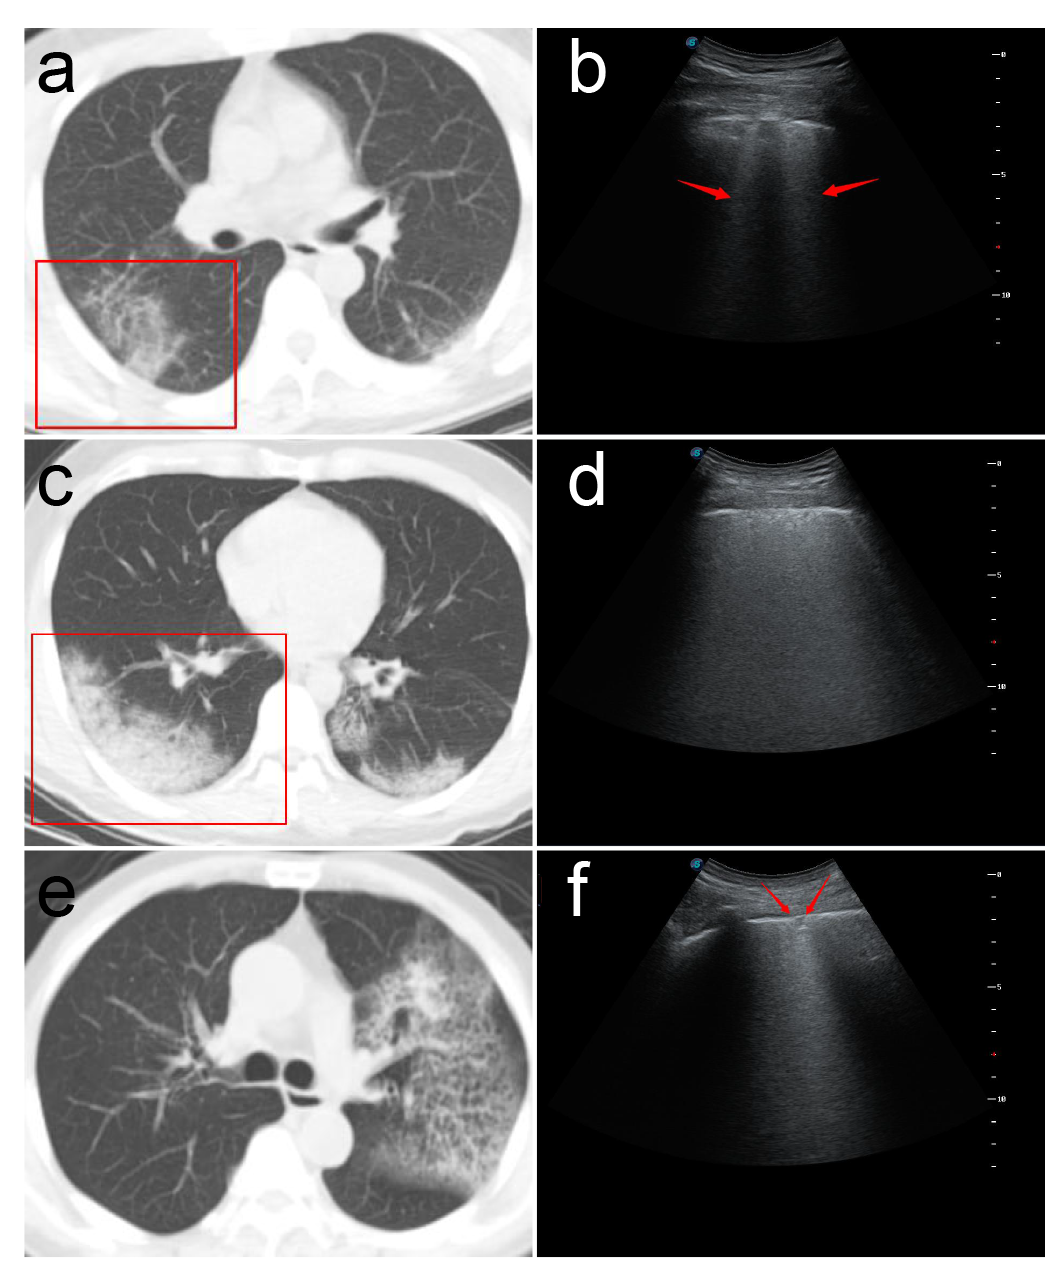

2.超声探查可见胸膜线下多条不连续或连续融合B线(瀑布征),或弥漫性B线(白肺征),同时A线消失。与心源性肺水肿所致B线比较,冠肺B线融合现象更普遍,位置相对也比较固定,B线边缘模糊,无分叉征,起点位于胸膜下病灶较肺水肿B线起点圆钝(凸阵探头)。

3.高频超声显示胸膜线欠光滑、毛糙,连续性中断,主要是由于胸膜下肺泡及间质病变气体含量减少,声波反射减少所致。

4.胸膜下病灶可见多发小斑片样实变,长条样实变。

5.病灶内回声均匀或不均匀,多可见细小支气管肺泡充气征(早期、进展期多见。考虑次级肺小叶受间质炎性侵犯,间质水肿增厚,部分细小支气管及肺泡尚未受侵犯气体含量高所致)或支气管充气征(重症期或局部大片实变多见,考虑原因可能为局部炎症风暴所致大部细小支气管肺泡水肿实变仅留较大支气管或部分肺泡所致伴病灶后弥漫性B线,经观察部分发病时间较长病情趋于好转冠肺患者CT影像呈小结节样实变影,超声亦可见胸膜下结节样不规则回声影,后见融合B线,位置固定。

6.高频超声还可显示病变肺周的胸膜局限性增厚及胸膜下病变周围局限胸腔积液(线阵探头更清晰多数患者胸膜增厚约1-2mm,病灶周胸腔内局限性胸膜下积液约2-3mm)随病情进程有所变化。